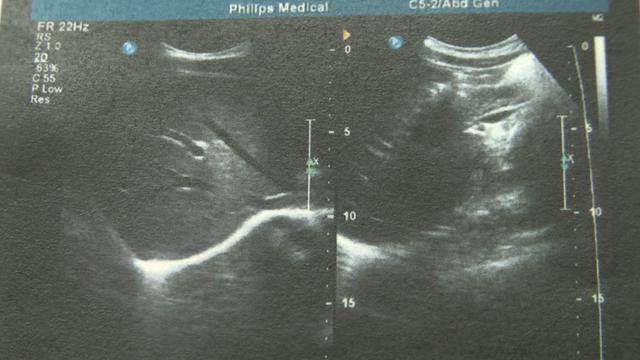

经过一段时间的治疗,小女孩的肝肾功能已经逐渐恢复,肺部纤维化也得到控制,今天上午,从ICU转到了普通病房。

南京儿童医院医生葛许华表示,百草枯中毒治疗通过血液灌流和血液滤过、透析等这样的方式,尽快的清除她体内药物毒素。因为这个小孩来的时候中毒时间比较长了,做这样的治疗已经不适合,医院目前给她的治疗是免疫抑制剂的治疗。

包括“尿素”在内,小女孩十几个生理指标都超过了正常水平十倍以上!所幸摄入毒量微弱,医院采用大剂量激素用药等方法,最终控制了病情。医生提醒,一般农药中毒的起初症状是有恶心呕吐现象,口腔会有溃疡,严重时还有昏迷,此时,如果家人发现孩子有接触农药可能,应第一时间送当地医院洗胃,然后再转到有能力救治的医院。